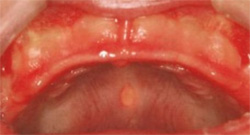

ベドナーアフタ

- [好発年齢・性差]

- 新生児期にみられることが多い。

- [好発部位]

- 口蓋粘膜にみられる。

- [症状]

- 硬口蓋粘膜に不定形の潰瘍がみられる。硬い哺乳瓶の乳首、目の粗いガーゼなどで 不注意な口腔清掃などの機械的刺激を与えたことによってできる。周囲に発赤を伴い、痛みがあるため授乳困難となることがある

- [治療]

- 原因となっている刺激を取り除く。刺激がなくなると自然に治癒する。副腎皮質ステロイド軟膏を塗布し、痛みや炎症を抑えることも有効となる。